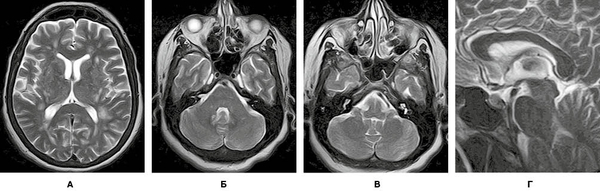

Завдяки виконаному МРТ-дослідженню головного мозку візуалізувано множинні вогнища, переважно овоїдної та округлої форм, розташовані в глибокій білій речовині обох семіовальних центрів. Вогнища гіперінтенсивні в режимах Т2/Flair і Т2, поліморфні. Типовою клінічною ознакою, характерною для перебігу ГРЕМ, на відміну від РС, є те, що більшість запальних вогнищ накопичують контраст. На зображеннях у режимі Т2 GRE не виявлено даних, які б могли свідчити про крововиливи в структурі вогнищ. МРТ-зображення головного мозку пацієнта в різних режимах, представлені на рисунках 6-9, підтверджують діагноз ГРЕМ.

Підписатися/images/nn257-1622023r6_.jpg)

/images/nn257-1622023r7_.jpg)

/images/nn257-1622023r8_.jpg)

/images/nn257-1622023r9_.jpg)